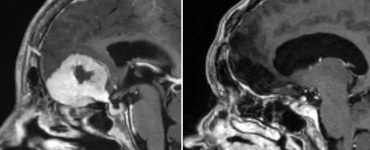

News Asportato un grosso tumore al cervello passando dalle sopracciglia: prima mondiale senza craniotomia Emanuela B.24/08/2025